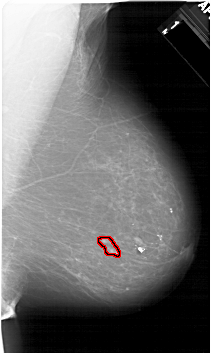

A_1597_1.RIGHT_MLO

RIGHT_CC LINES 6211 PIXELS_PER_LINE 3526 BITS_PER_PIXEL 12 RESOLUTION 43.5 OVERLAY

FILE: A_1597_1.RIGHT_MLO.OVERLAY

TOTAL_ABNORMALITIES 1

ABNORMALITY 1

LESION_TYPE CALCIFICATION TYPE PLEOMORPHIC DISTRIBUTION LINEAR

ASSESSMENT 4

SUBTLETY 2

PATHOLOGY MALIGNANT

TOTAL_OUTLINES 1

BOUNDARY